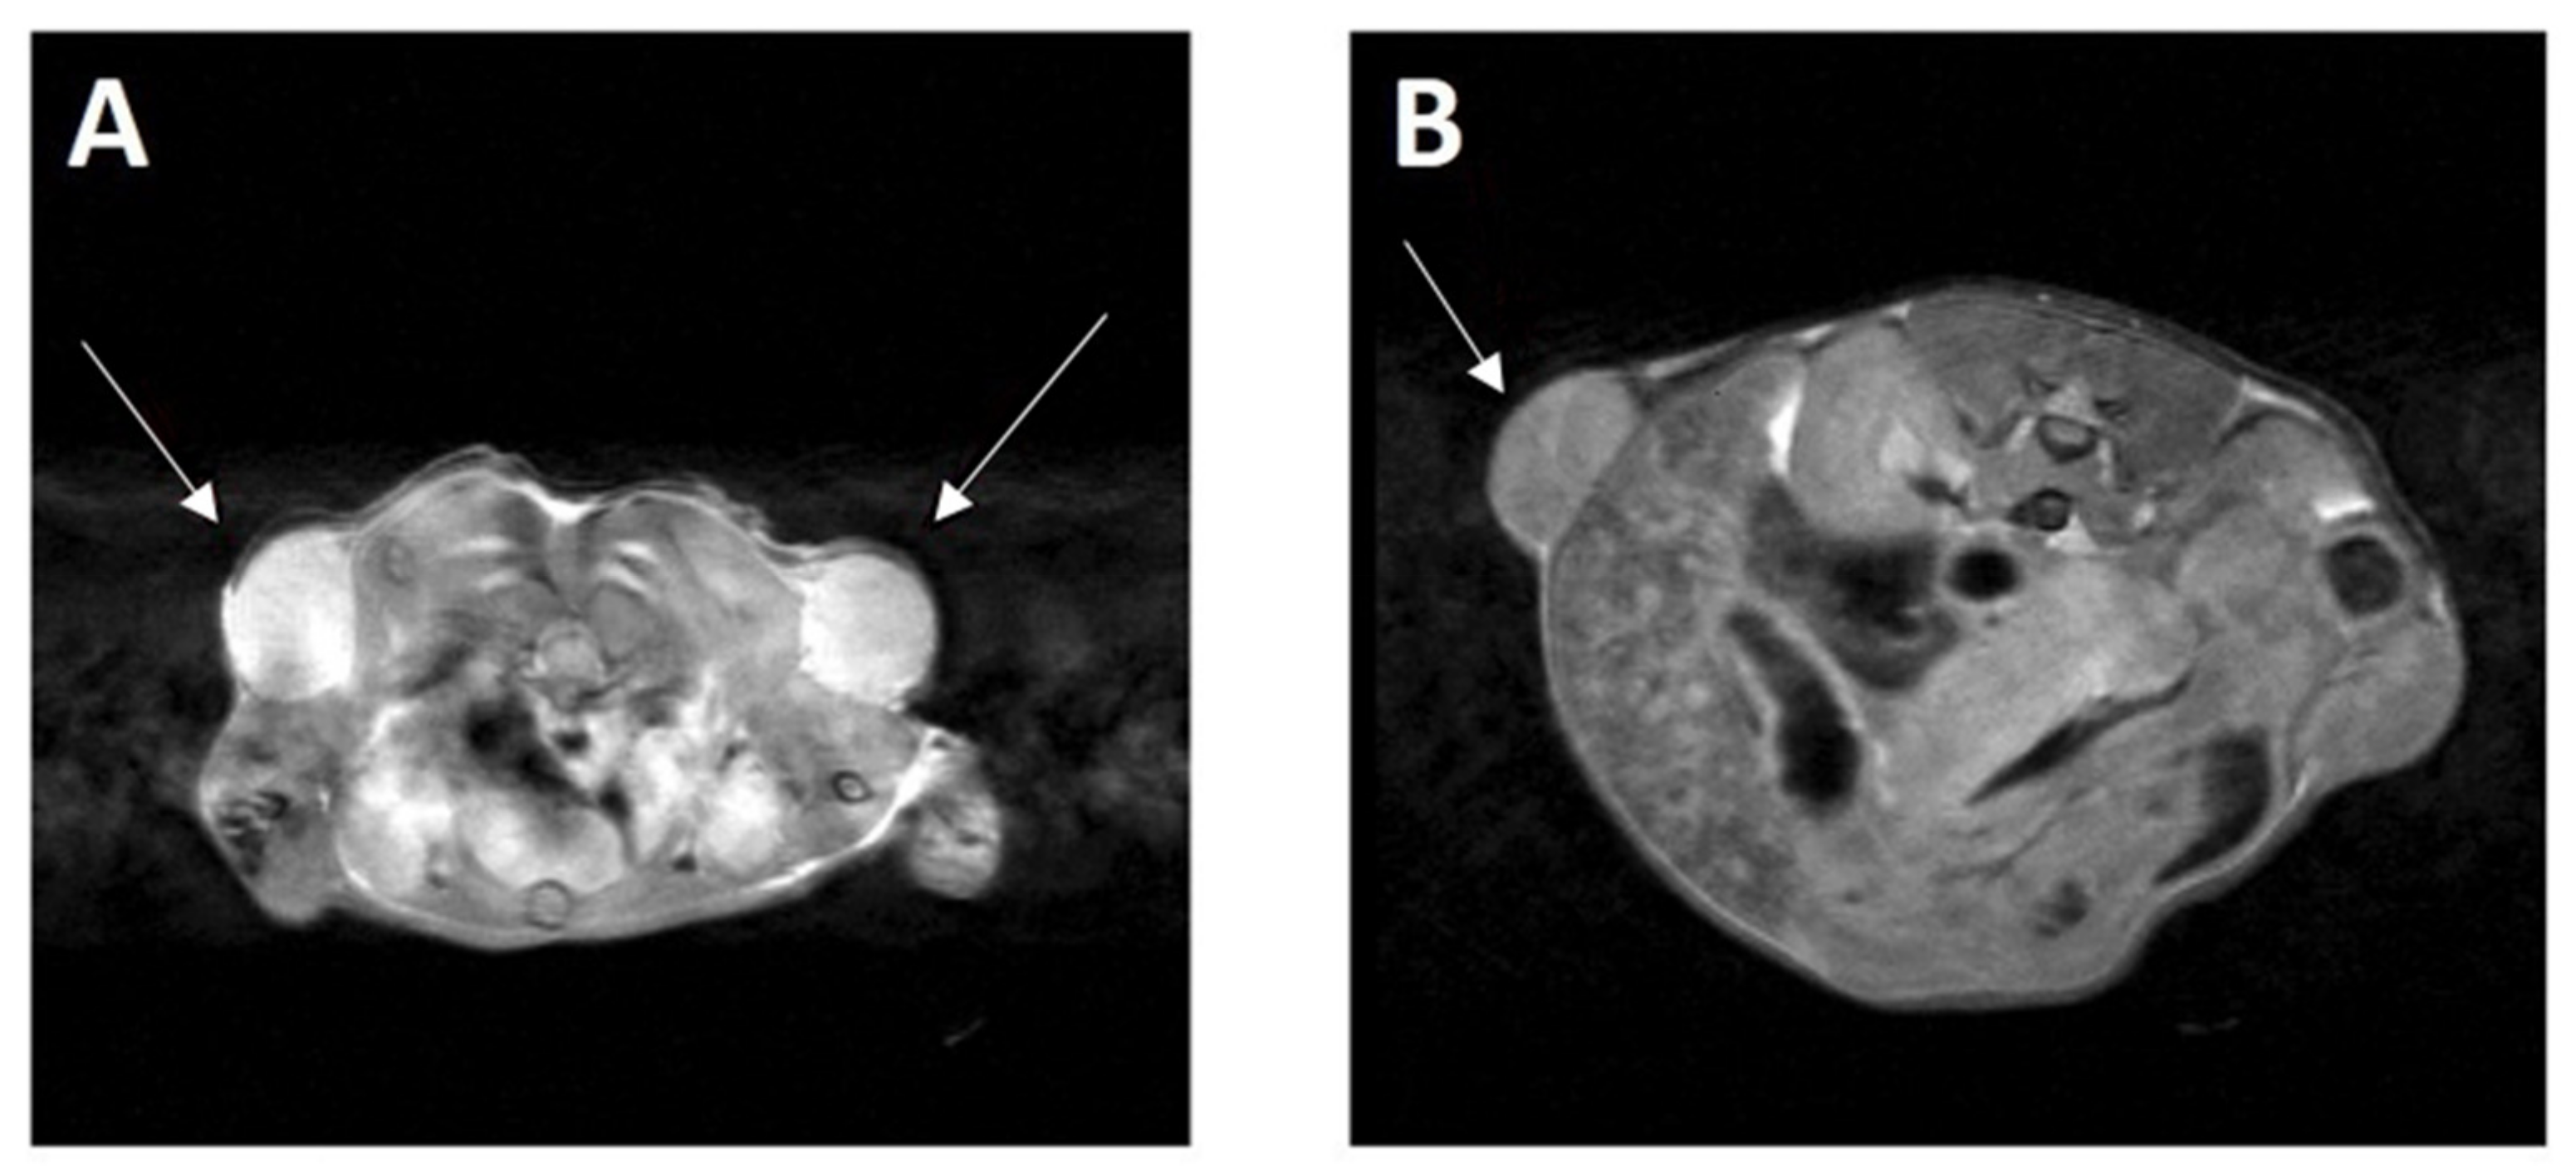

2.5. Diagnosis of Hematologic Malignancies

4.3. Magnetic Resonance Imaging (MRI)